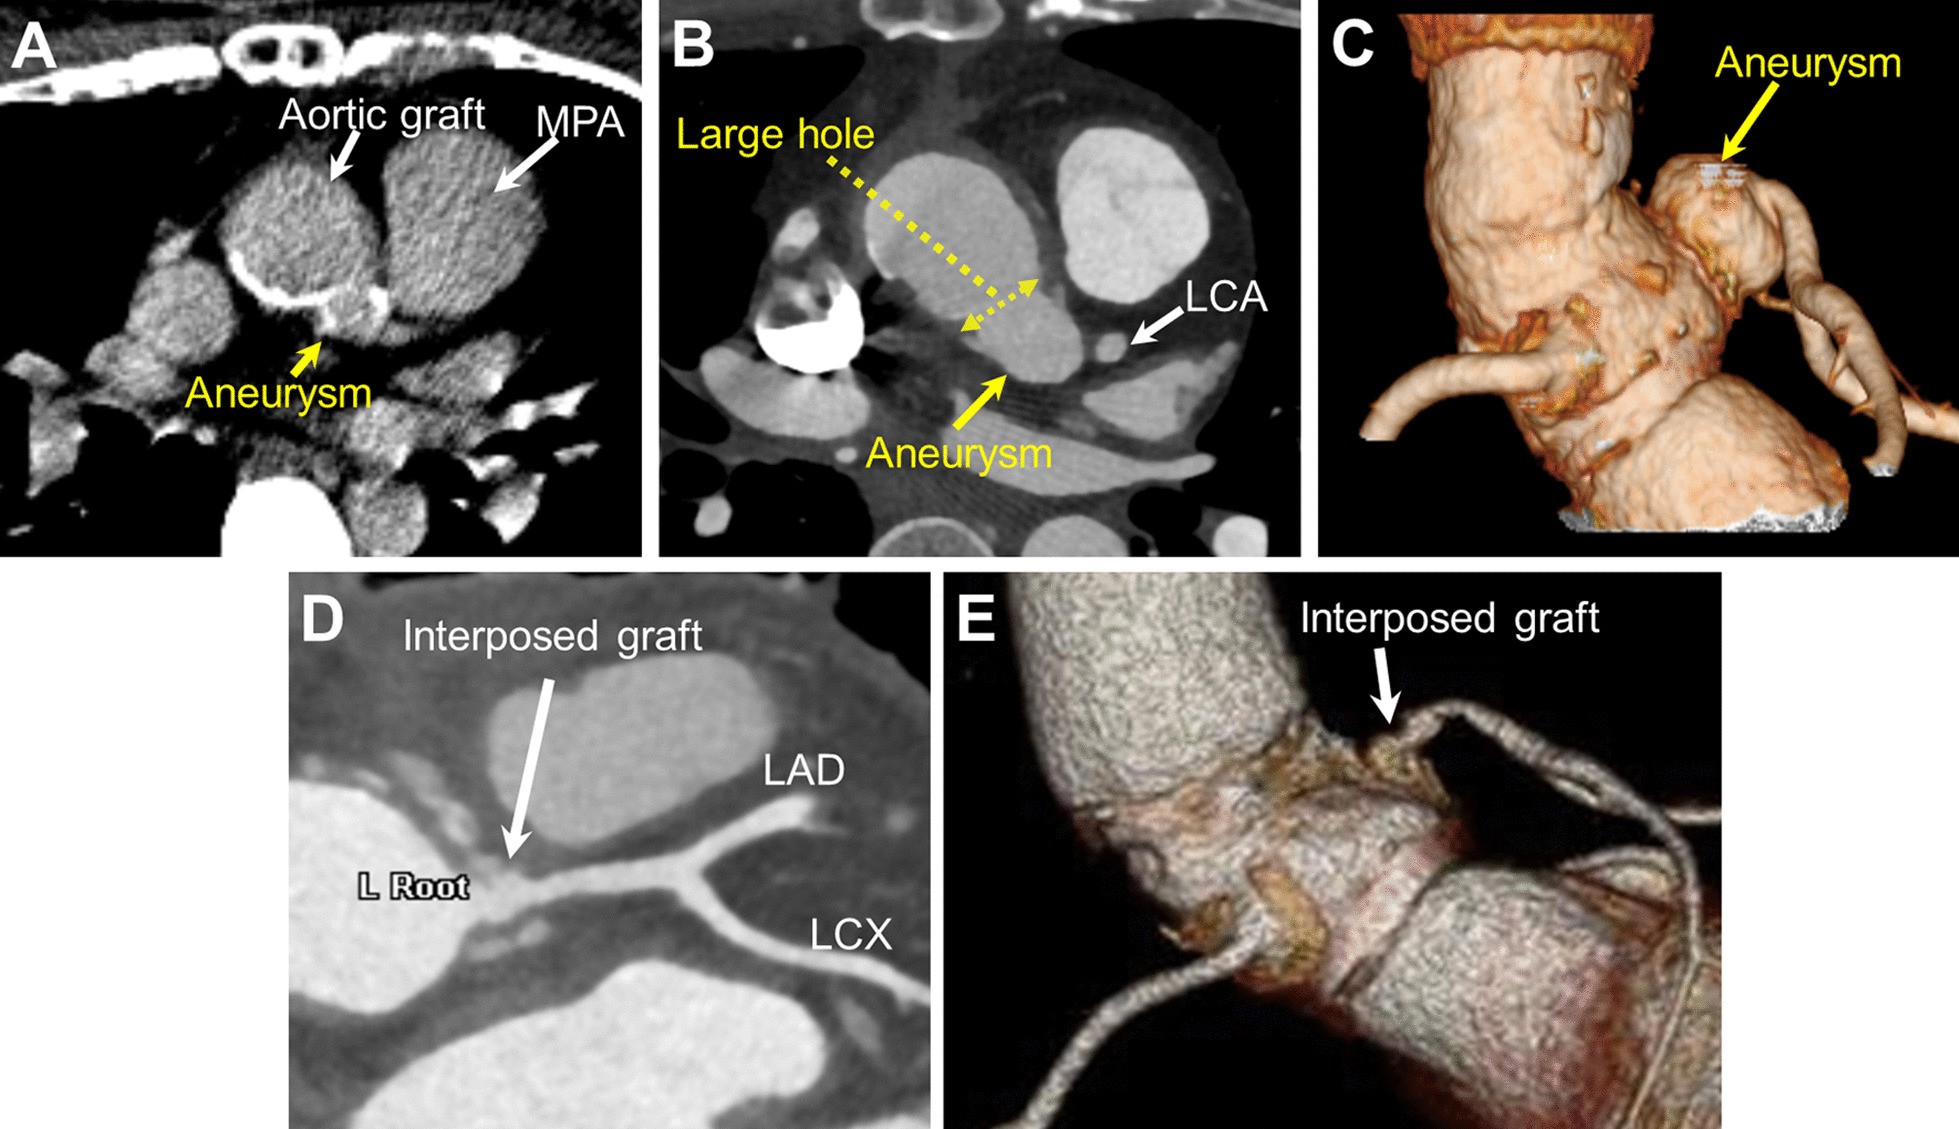

Fig. 1

From: Left coronary button aneurysm presenting with progressive enlargement after aortic root replacement

A Computed tomographic (CT) image 14 years after aortic root replacement shows the LCA button aneurysm with a diameter of 10 mm. B CT image 24 years after aortic root replacement shows that the LCA button aneurysm gradually enlarged to a diameter of 20 mm. C Preoperative three-dimensional reconstructed CT image shows the LCA button aneurysm. D, E Postoperative CT image shows successful reconstruction of the LCA system. LAD: left anterior descending artery, LCA left coronary artery, LCX left circumflex artery, MPA main pulmonary artery